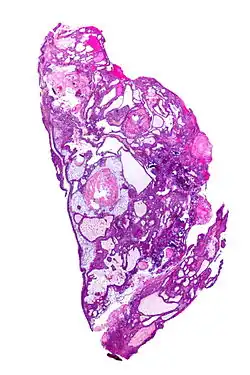

| Very low magnification micrograph of an adamantinomatous craniopharyngioma. HPS stain. | |

On macroscopic examination, craniopharyngiomas are cystic or partially cystic with solid areas. On light microscopy, the cysts are seen to be lined by stratified squamous epithelium. Keratin pearls may also be seen. The cysts are usually filled with a yellow, viscous fluid rich in cholesterol crystals. Of a long list of possible symptoms, the most common presentations include headaches, growth failure, and bitemporal hemianopsia.

Micrograph showing the characteristic features of an adamantinomatous craniopharyngioma - cystic spaces, calcifications, and "wet" keratin, HPS stain -